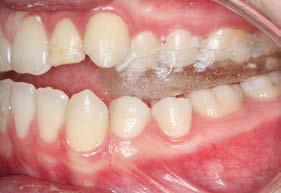

Figura 3. Lateral derecha. Figura 4. Izquierda de inicio. Figura 5. Frente. Figura 6. Overjet, laterales derecha e izquierda.

Las fotografías intraorales muestran las relaciones molares clase II y las relaciones caninas clase II bilaterales (Figura 3 y 4), espaciamiento anterosuperior, un overjet y overbite aumentado (Figura 5). La forma de los arcos es cuadrada, superior e inferior, con el apiñamiento moderado inferior y los espacios en superior.

Figura 12. Panorámica de progreso. Figura 13. Frente, derecha e izquierda de progreso

En los estudios intraorales de progreso en la fotografía de frente se observa la mejoría el overjet y overbite (Figura 13), así como la coincidencia de las líneas medias dentarias. Se obtuvo las relaciones clases I caninas y molares para la obtención de la máxima intercuspidación, y para el paralelismo radicular se utilizaron arcos de acero, así como la oclusión funcional, con el detallado rectangular 0.019 × 0.025 superior e inferior, dobleces de primer, segundo y tercer orden y elásticos en W.